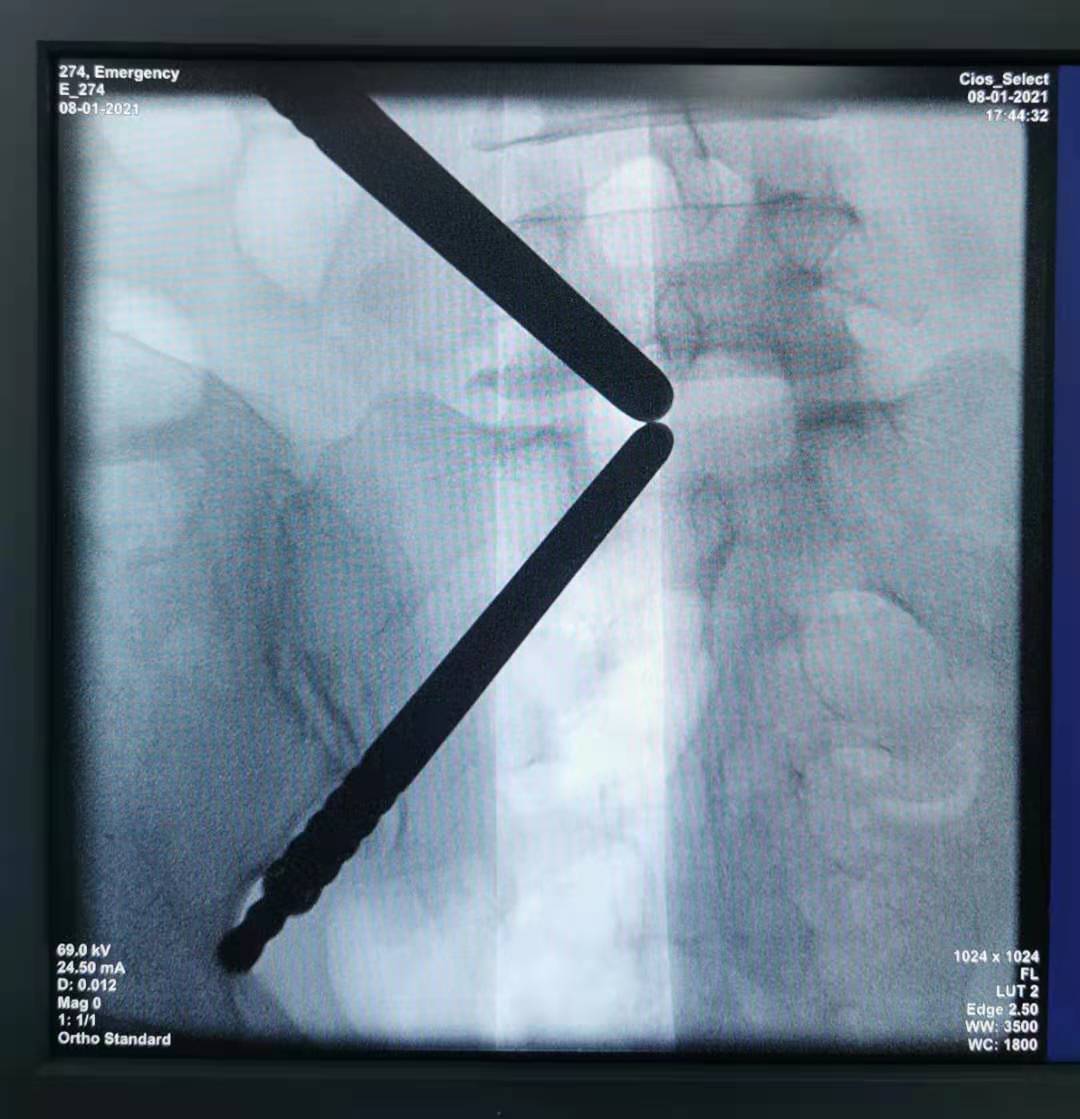

入院来,患者腰及右下肢疼痛难忍,只能膝胸位趴在床上,完善检查发现患者为腰5/骶1椎间盘突出(巨大型)。由于患者疼痛难忍,不能耐受常规局麻下内镜手术,为解决患者的痛苦,使患者尽快康复。椎间盘中心团队为患者制定了全麻下UBE技术椎板开窗椎间盘髓核摘除术。

术中

术中取出髓核组织